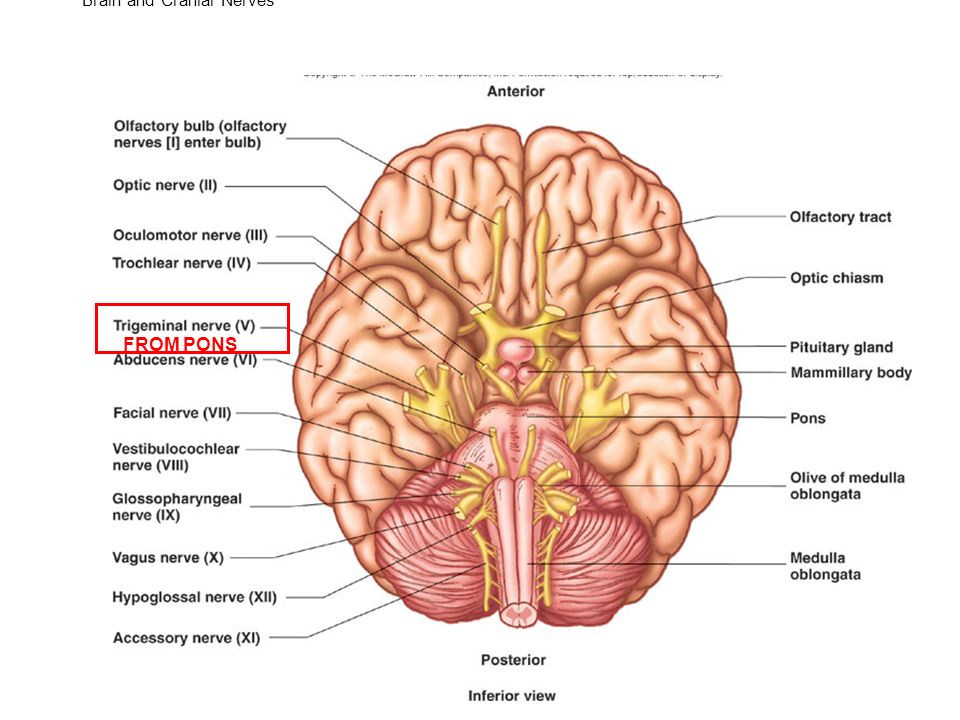

Анатомические снимки верхнелатеральной поверхности головного мозга